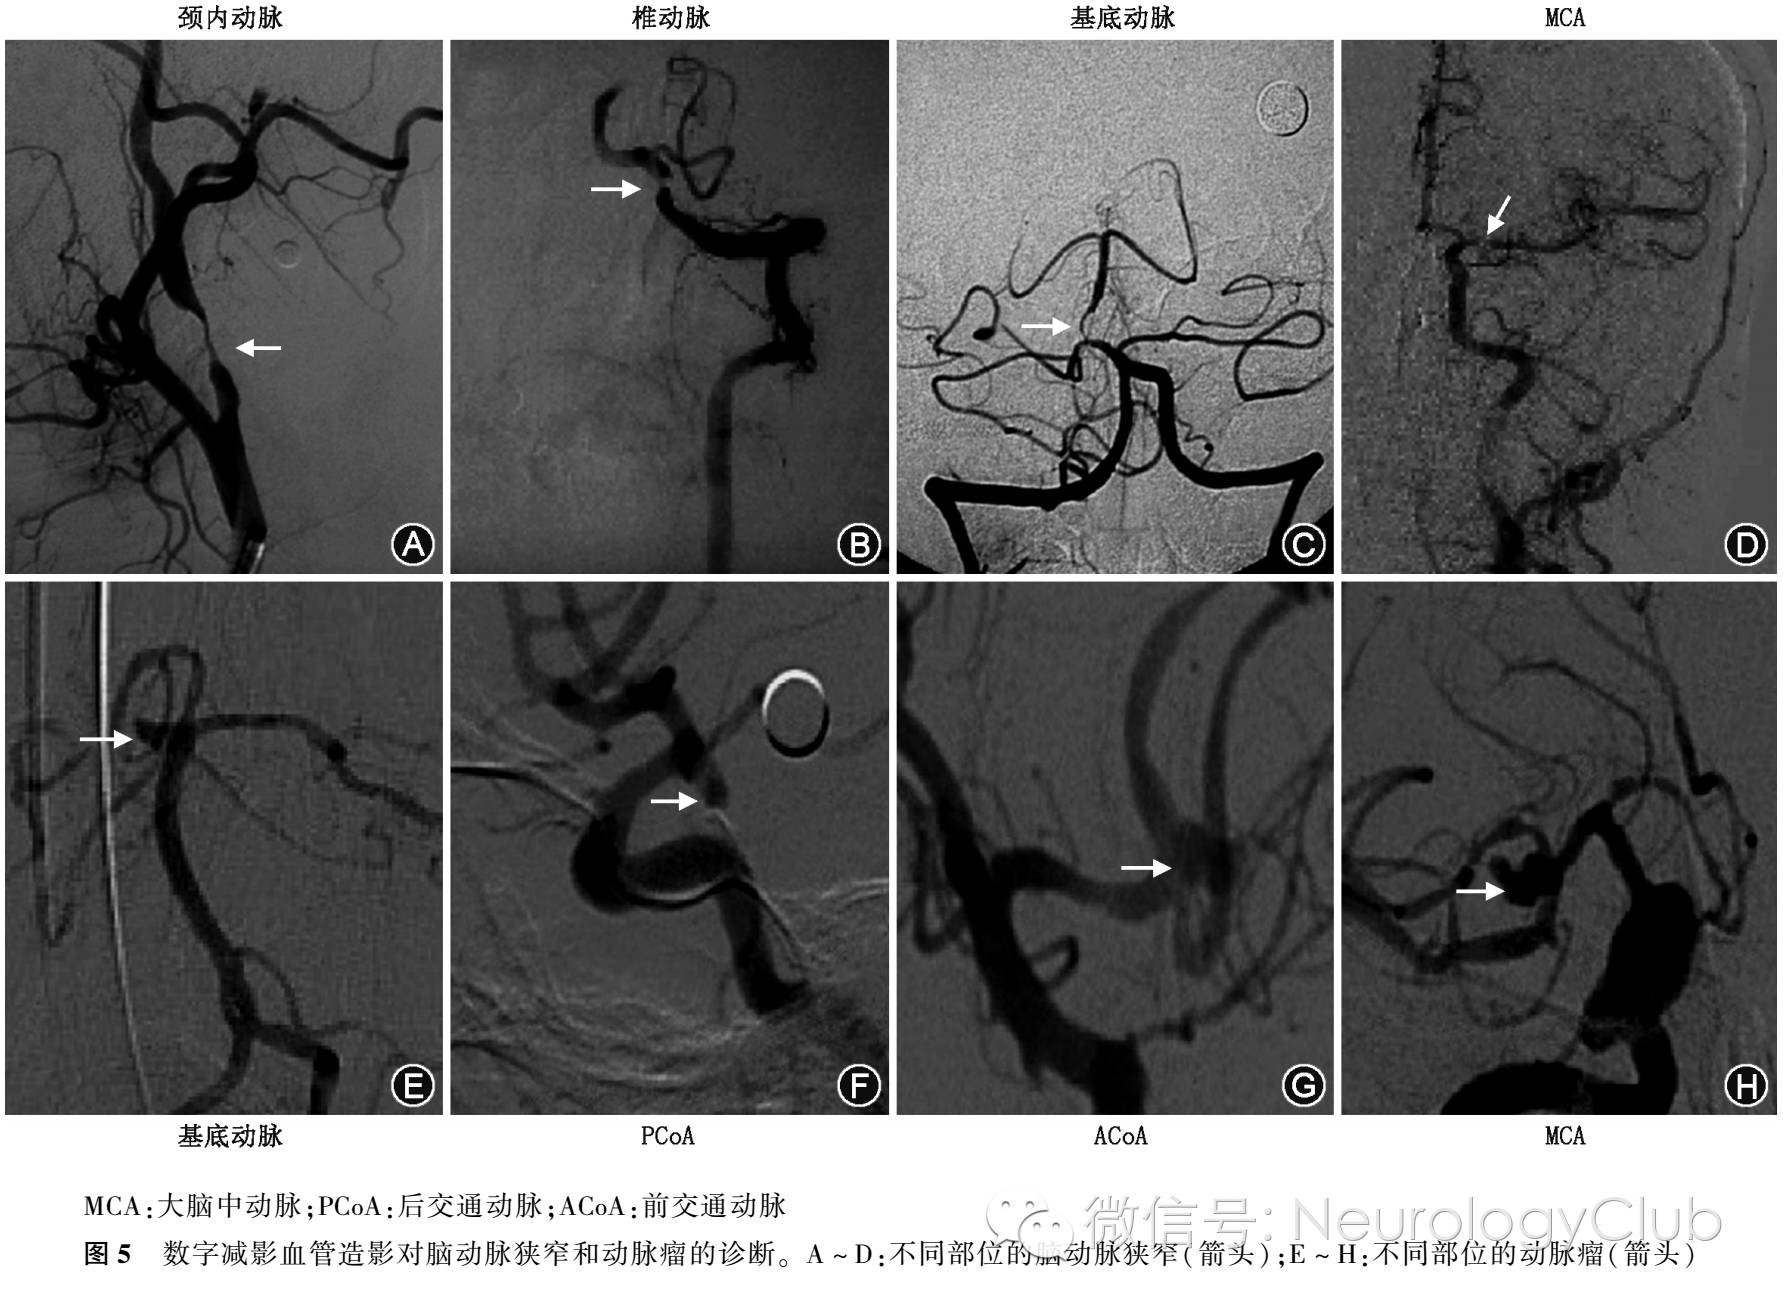

DSA通过对血管造影进行数字化处理,保留血管影像,从而可以清晰观察血管病变情况,为临床提供真实的立体图像,并为介入治疗提供依据,为目前血管病诊断和治疗不可或缺的一项影像技术,一直是多种脑血管疾病诊断的“金标准”,其准确性、敏感度、特异度均较无创性检查手段高。但其缺点在于耗时长,患者及医务工作者同时受到电离辐射,并且因其有创性的操作可能导致严重的并发症甚至死亡,使DSA技术在临床应用中受到一定限制。DSA能够清晰显示自主动脉弓至整个颅内各级血管及其分支的位置、形态等,能准确地评估血管狭窄、动脉瘤及侧支循环代偿(图5)。Agid等建议对于CTA阴性的SAH患者,应完善DSA检查。

(一)DSA对颅内外动脉狭窄和动脉瘤的诊断

DSA能真实地显现脑血管形态、结构和循环时间,可清楚显示动脉管腔狭窄(图5A-D)、闭塞以及侧支循环等情况,还能明确粥样硬化斑块表面是否有溃疡形成,以及各种动脉瘤(图5E-H),对缺血性脑血管病患者以及动脉瘤是否采取介入治疗起着重要的指导作用。目前DSA仍是诊断颅内动脉狭窄或闭塞,以及动脉瘤的“金标准”,但由于各种非侵袭性检查技术的不断完善,在诊断颅内动脉狭窄方面有可能逐步取代DSA。